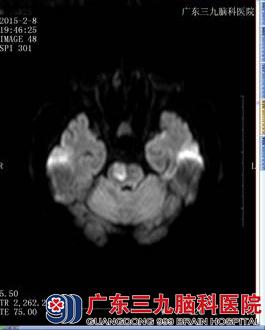

入院后2015年2月9日头颅MRI示桥脑右侧偏急性期脑梗塞灶(图一)。高血压四项示:血管紧张素I 4ng/ml,血管紧张素II 80.75pg/ml,肾素活性2.61ng/ml/h,醛固酮914.48pg/ml。离子三项示钾 3.39 ↓ mmol/L、钠 140.7 mmol/L 、氯 103.3 mmo/L。进一步完善肾上腺CT示左侧肾上腺增生(图二)。结合患者长期高血压、低血钾、醛固醇高及左侧肾上腺增生,目前高血压考虑为原发性醛固酮增多症引起的症状性高血压。诊断为:1、脑梗塞(桥脑,急性);2、高血压病(3级,极高危组)?3、原发性醛固酮增多症?给予醛固酮拮抗剂螺内酯降压,氢氯吡格雷抗血小板聚集,阿托伐他汀钙抗动脉硬化等治疗1周。血压波动大得到控制,左侧肢体无力较前明显好转。出院后患者头痛头晕缓解,肢体活动较前好转,遂回家继续治疗。

头颅MRI弥散(图一)